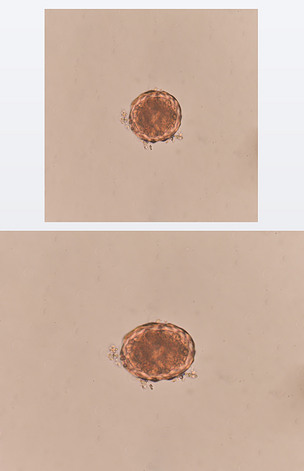

图注:显微镜下的蛔虫受精卵

图3. 感染性蛔虫卵(罗嫚供)